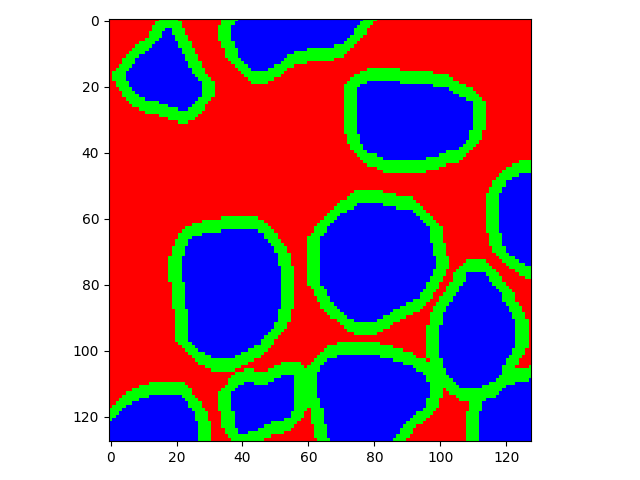

The task of nuclei segmentation can be roughly divided into two stages: the first stage is extracting the foreground(nuclei), the second stage is segmenting the connected foreground area into separated nuclei and finding out the boundary of each nucleus. Our method intends to merge these two steps by extracting the nuclei and their edges at the same time. That is the reason why it is named ”nuclei-boundary(NB) model”. As shown in Fig.3, the output of the NB model has three channels, each has the same height and width with the input image. Its values represent the probabilities of each pixel being , or class, respectively. The manual annotation for our segmentation problem is the boundary of each nucleus. A pixel belonging to the class means that it is on or inside an annotated boundary and within 2 pixel from the boundary. Pixels of the class are those that are inside annotated boundary but are not pixels. Correspondingly, the output can be regarded as an RGB image and the estimated maps of the , and are represented by red, green and blue, respectively, as shown in Fig.3. To generate the ternary mask for training, we apply a morphology operator to each nucleus to obtain the pixels, and then subtract pixels from the nucleus to get pixels.

Figure 6 shows how our method segments the nuclei step by step. The color variety is well controlled by the color normalization procedure. The prediction result shows clear nuclear areas and nucleus boundaries. In the final segmentation result and ground truth image, each nucleus is represented by a different color.